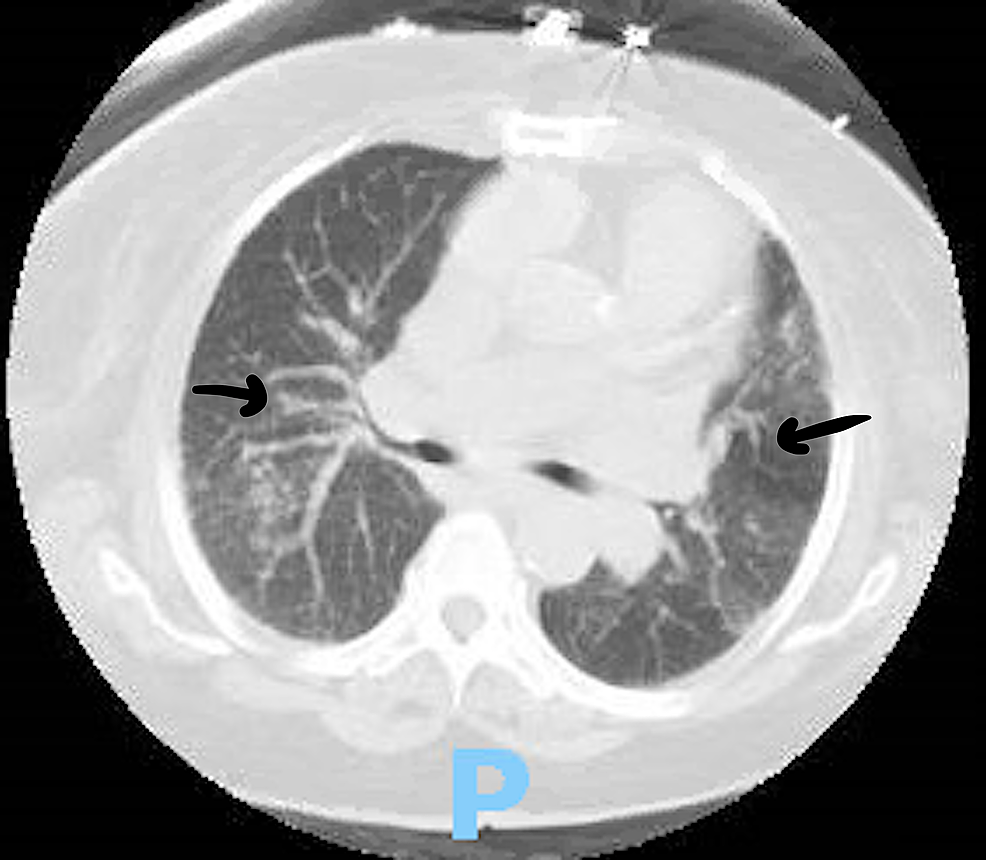

Interstitial Lung Disease Ct Scan

Interstitial Lung Disease Ct Scan Ild Radiology Articles Interstitial lung disease (ild) is a term used to describe a heterogeneous group of lung disorders with characteristic. Magnetic resonance imaging (mri) has been emerging as an imaging modality to assess interstitial lung diseases (ild). The objective of this article is to provide a review of fild with an emphasis on. An optimal chest mri protocol for ilds. Ild Radiology Articles.